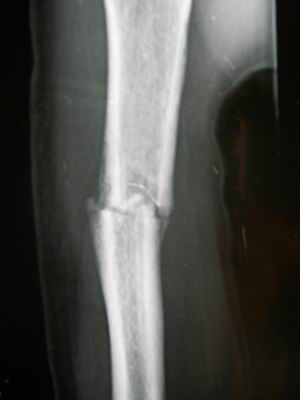

已经有骨性的愈合,但是骨髓腔还没有开通,骨皮质也还没有长好